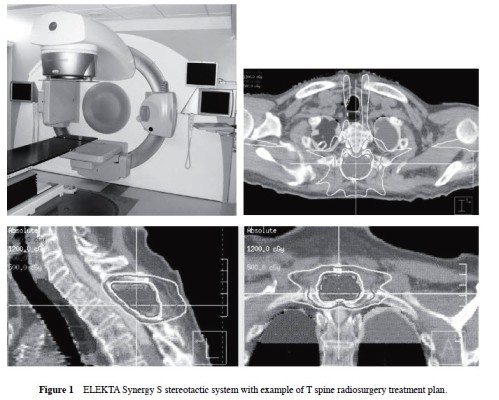

One hundred seventy-nine spine lesions were treated using the Elekta Synergy S 6-MV linear accelerator with a beam modulator and CBCT image guidance combined with a HexaPOD couch (Figure 1) that allows patient positioning correction in 3 translational and 3 rotational directions. Lesion location included 29 cervical, 76 thoracic, 52 lumbar, and 22 sacral. There were 146 malignant and 33 benign lesions. Twenty-nine lesions (16 %) were intradural. One hundred twelve lesions (63 %) had received prior conventional fractionated radiotherapy.

Single fraction spine radiosurgery using the Synergy S was determined to be safe, feasible, and accurate. This technique provides for a translational intra fractional positioning accuracy of < 2.0 mm as observed in our study.